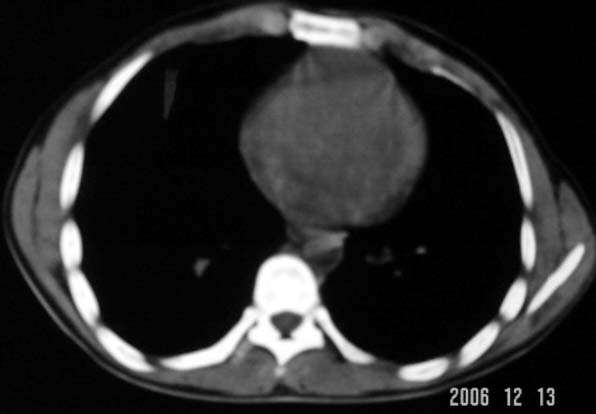

标题: CT5614:外伤病人男,20岁,右上腹痛.余肺野(-) [打印本页]

标题: CT5614:外伤病人男,20岁,右上腹痛.余肺野(-)

不象与外伤相关,请多给几幅图片和窗口?